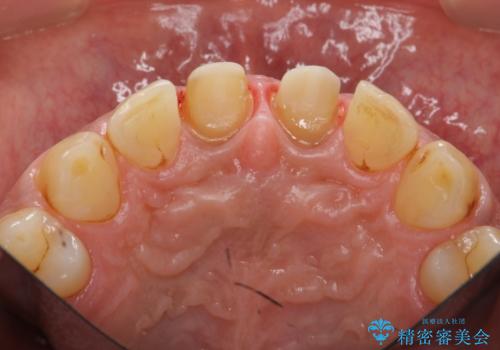

- 体調により前歯部の歯ぐきから出血や膿が出ることの改善を求めて来院されました。

X線写真より、根尖部に透過像が認められ根管治療・ファイバーコア築盛・セラミッククラウンの作製が必要な状態です。

歯ぐきからの出血・排膿について

歯ぐきからの出血・排膿がある場合、根管内の感染や 歯肉炎・歯の破折などが考えられます。

X線検査や歯周組織検査などを行い適切な治療を行うことで良好な結果を得ることができます。